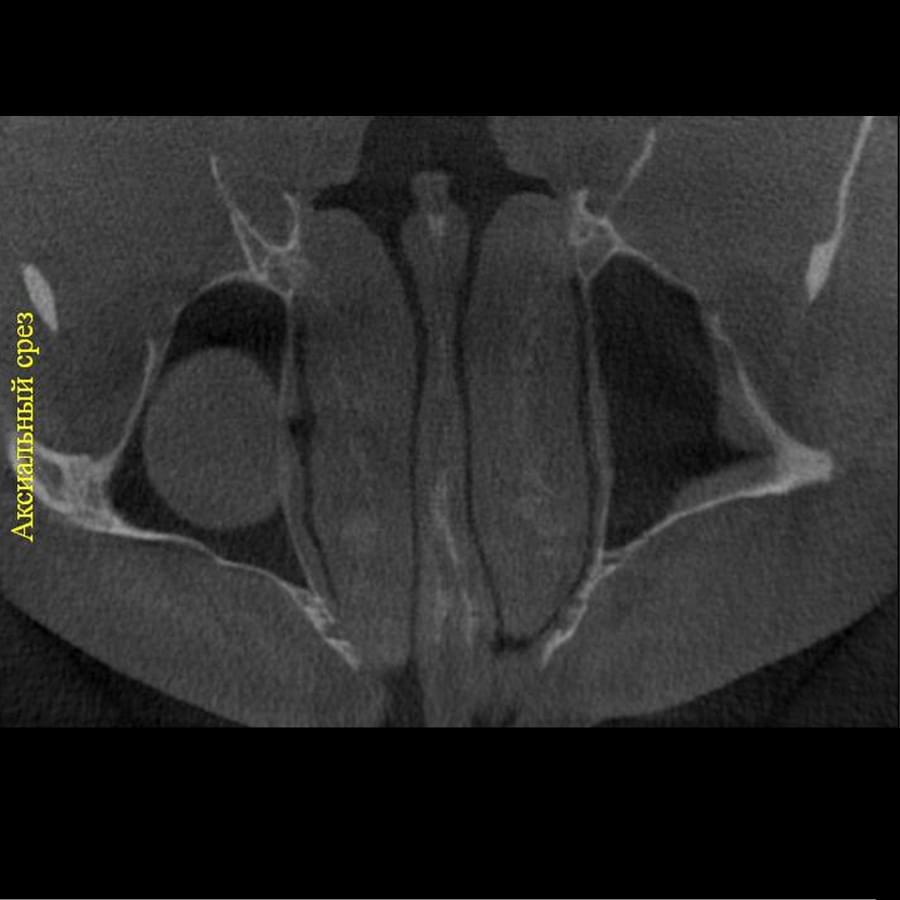

Отримайте вичерпну інформацію про стан ЛОР-органів завдяки надточній діагностиці на апараті

PLANMECA. Наші знімки дозволяють детально візуалізувати всі групи навколоносових синусів,

структури остіомеатального комплексу та анатомію носової перегородки.

Ми надаємо не просто знімок, а повний діагностичний сервіс:

Детальний опис: Кожне дослідження супроводжується професійним висновком лікаря-рентгенолога

з описом виявлених патологій (кісти, поліпи, сторонні тіла, рівень рідини, потовщення

слизової).

Зручна візуалізація: Можливість перегляду структур у будь-якій проекції (аксіальній,

корональній, сагітальній) для точної локалізації запального процесу.